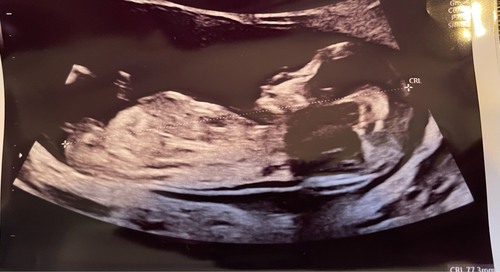

Ik deel hem nog eens, de meningen zijn verdeeld… 💙🩷?

12+6! 🥰 wat denken jullie?